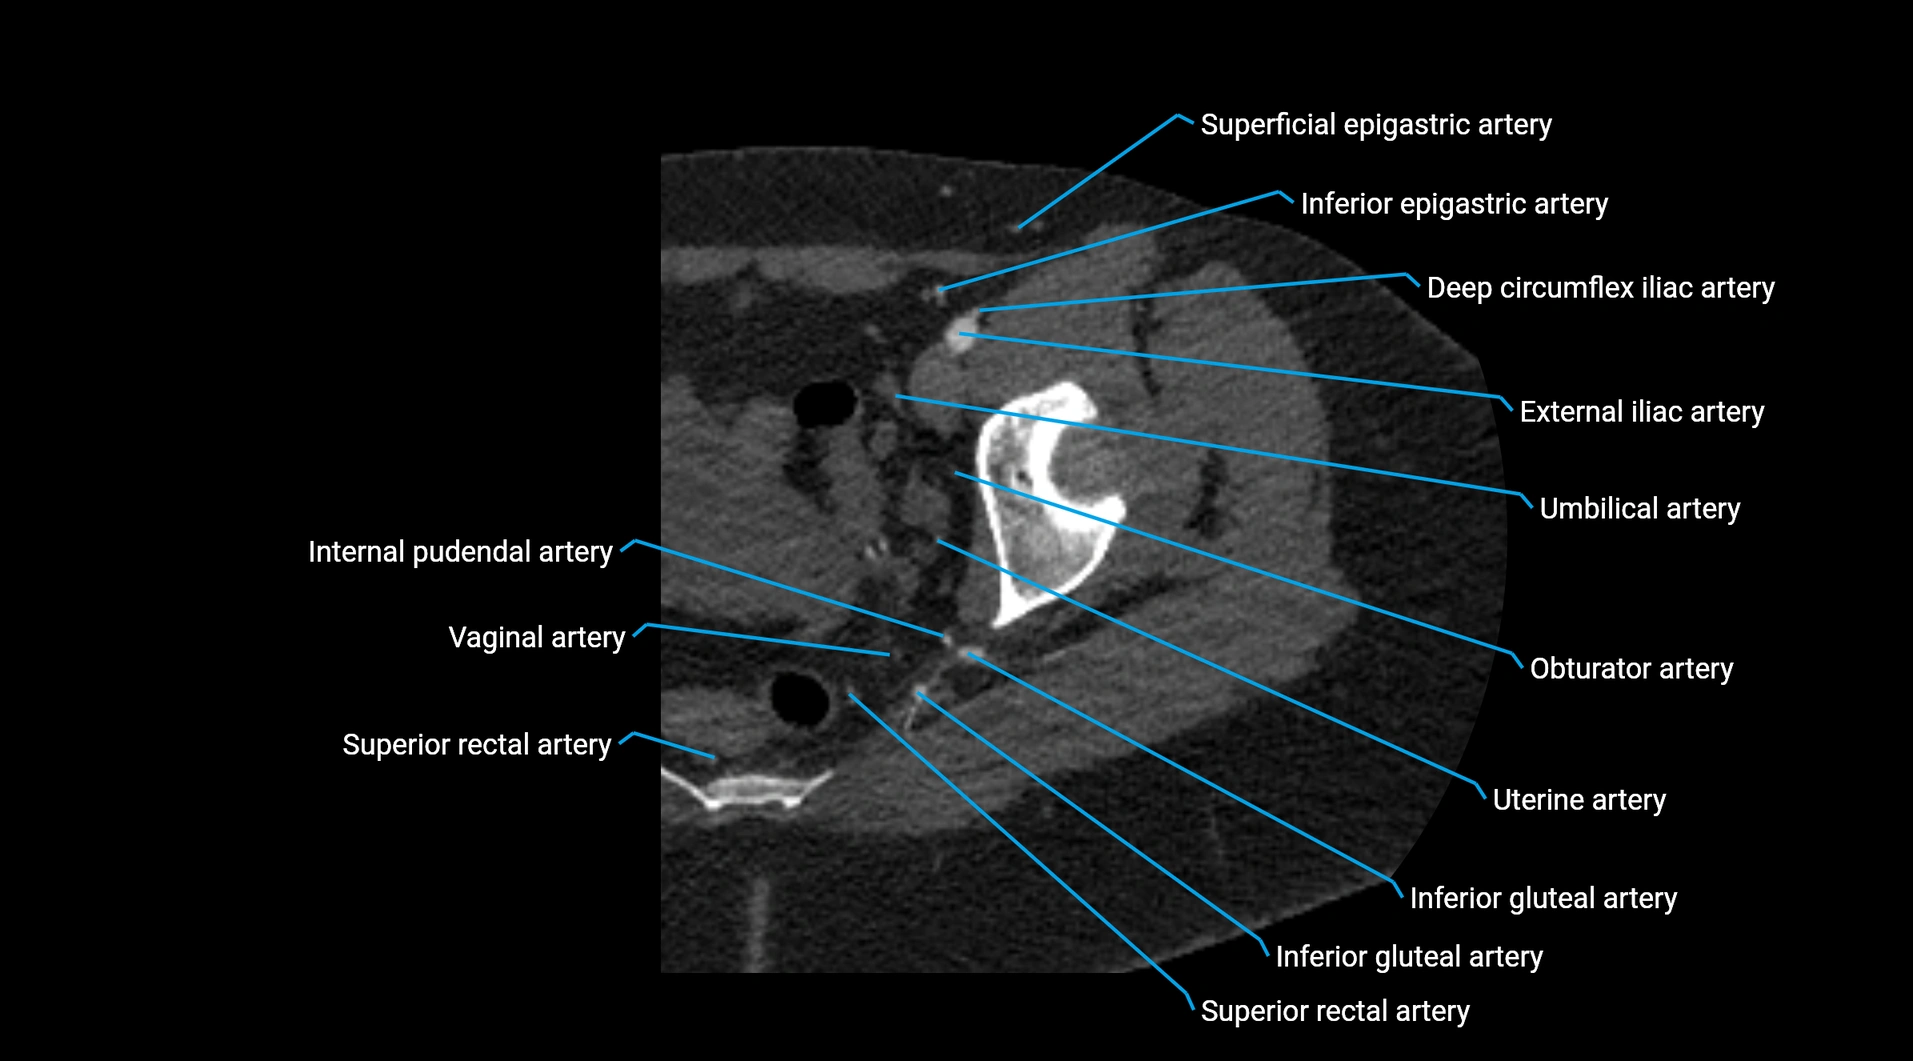

CT images

image